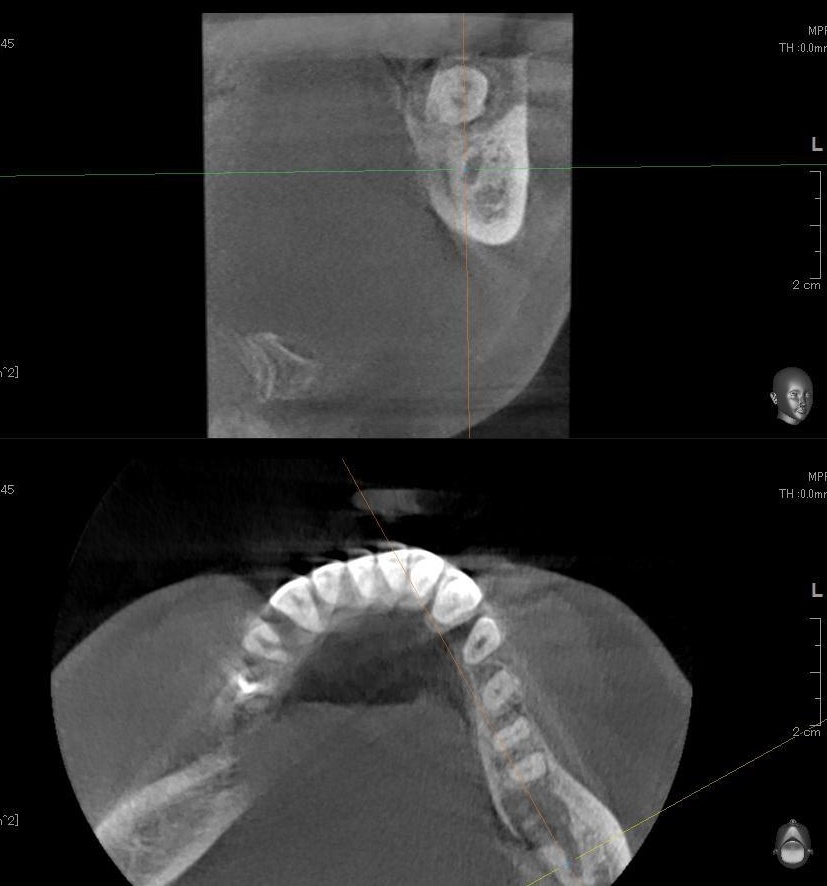

さらに、下顎の親知らずは下歯槽神経に非常に近いところに生えている場合もあるため、CTも撮影し詳しい解析を行います。

親知らずが生えている位置が、神経に近い、あるいは神経に当たっている場合は、大きな病院に紹介する場合もあります。

親知らずの根っこは下歯槽神経から近い距離にありますが、抜歯は可能との診断でした。